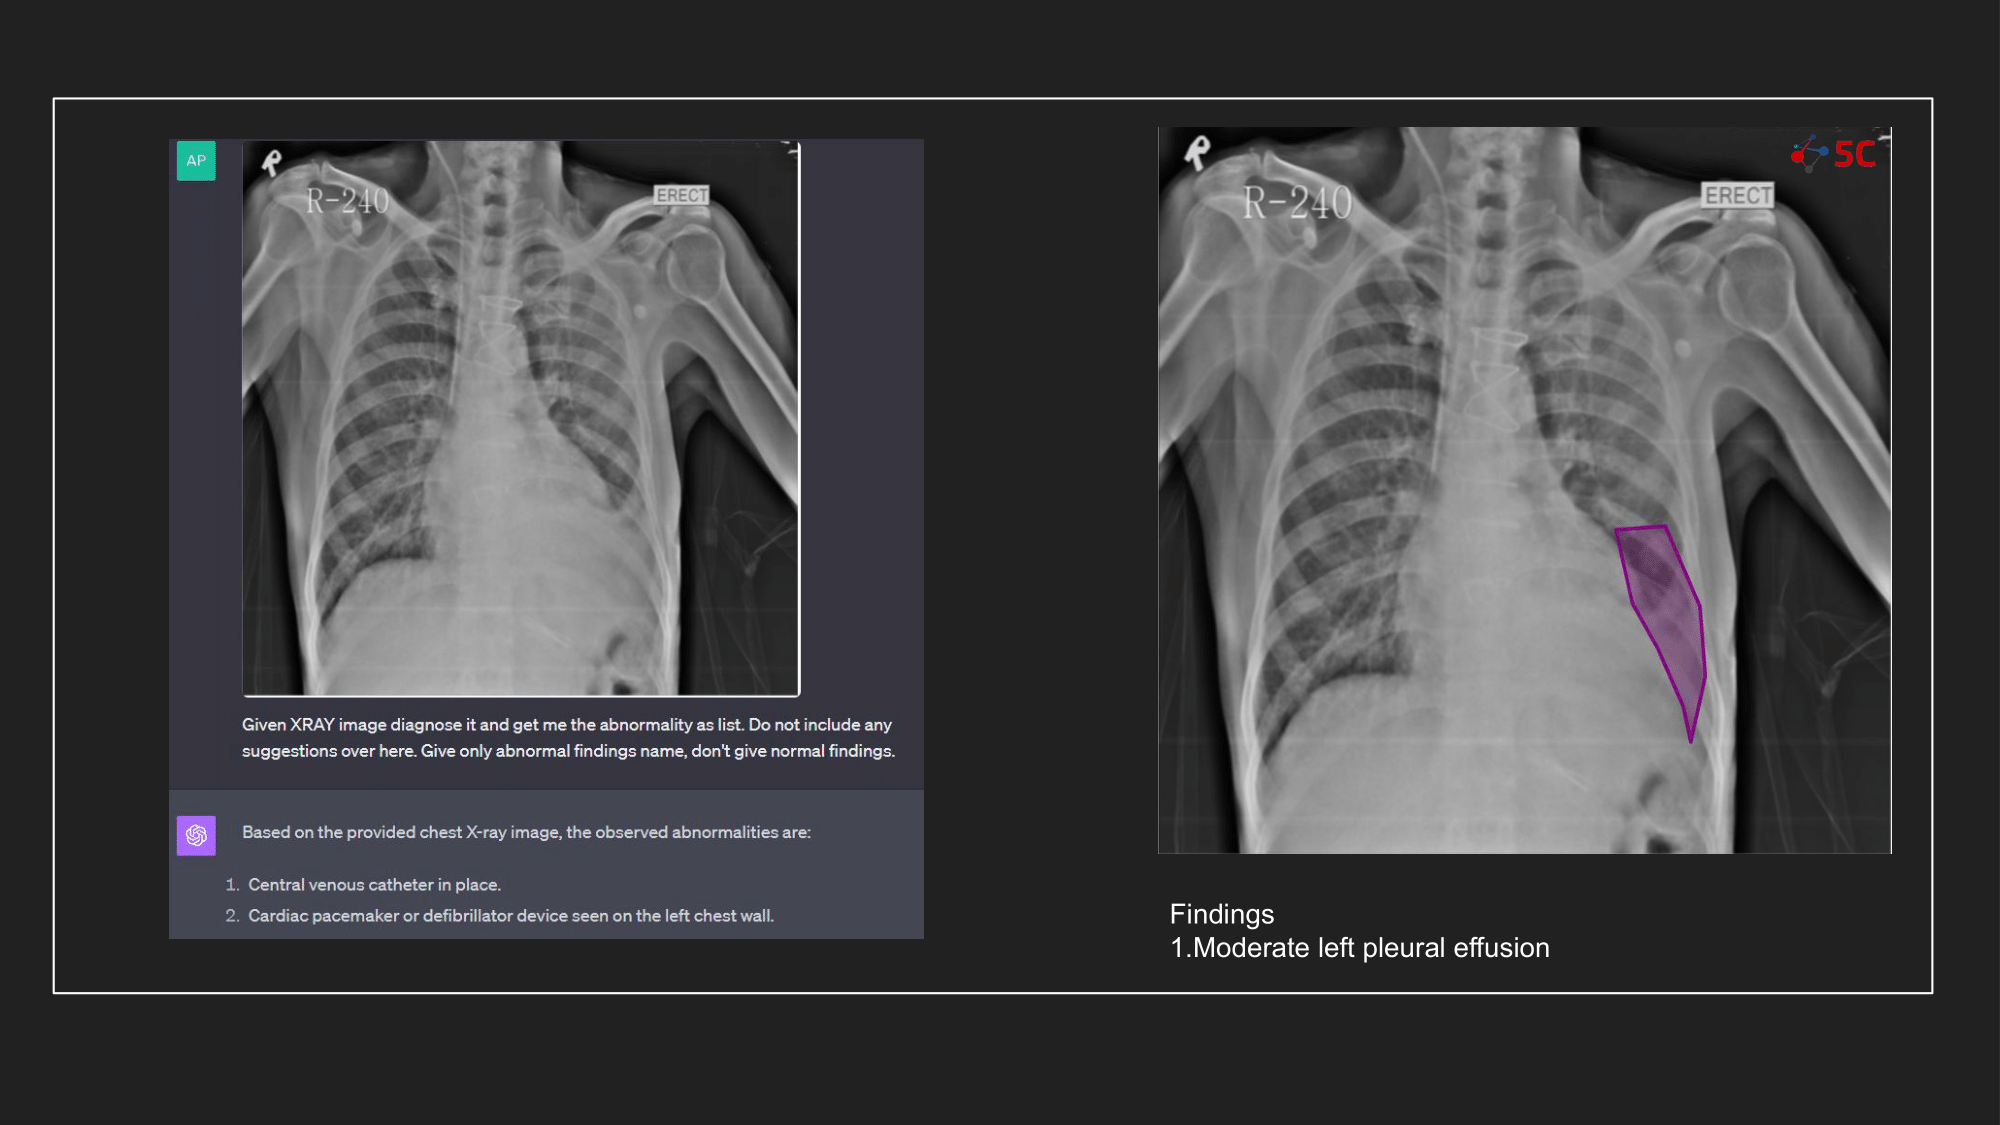

To gauge GPT-4V's prowess in detecting pleural effusion, an experiment was conducted with 10 random chest X-rays known to have pleural effusion. The XRays were sent to GPT-4V, Radiologists as well as to 5C's AI.

Presented below are the results from the experiment.

The output from GPT-4V and from 5C's AI model for the Chest XRays are provided at the end of the post.